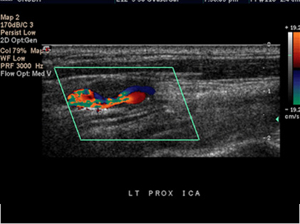

- 도플러 초음파 검사 (Duplex ultrasound)

- 하지정맥류 진단에 가장 중요하고 기본이 되는 비침습 검사입니다.

- 혈관 초음파로 혈관 구조를 확인하고 도플러를 통해 혈액의 흐름 방향, 속도, 역류 여부 및 역류 시간을 측정합니다.

- 이 검사를 통해 정맥 내 판막 손상 부위에서 혈액이 역류하는 정도를 평가하고, 정맥류의 원인이 되는 혈관을 정확히 찾아낼 수 있습니다.

- 도플러 초음파 검사 (Doppler Ultrasound)

- 일반 초음파의 원리에 도플러 효과를 적용한 검사로, 움직이는 혈액의 속도와 방향을 실시간으로 측정할 수 있습니다.

- 혈관 내 혈류의 특성을 분석해 혈류가 정상적으로 흐르는지, 역류나 협착이 있는지 평가할 수 있습니다.

- 혈관의 기능적 상태를 파악하는 데 중요한 역할을 하며, 하지정맥류, 동맥 협착, 혈전 등 혈관 질환 진단에 쓰입니다.